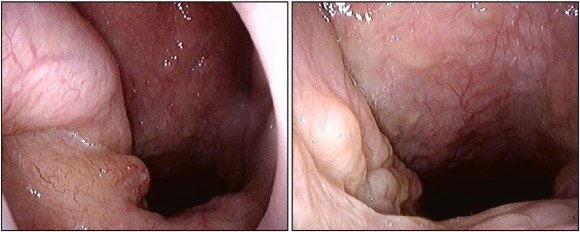

Interesting report from Michigan Otolaryngology on the importance of a broad differential for ear canal masses! Learn more about this mystery lesion which may be associated with Carney complex, and should be worked up for associated cardiac and endocrine abnormalities! cutt.ly/cjCjdx5

Remember to include amyloidosis in your differential for nasopharyngeal masses! Check out this case of a patient presenting with hearing loss, right exudative otitis media, and a nasopharyngeal mass. Learn more here: sciencedirect.com/science/articl… American Journal of Otolaryngology Headmirror.com OtoNotes.com